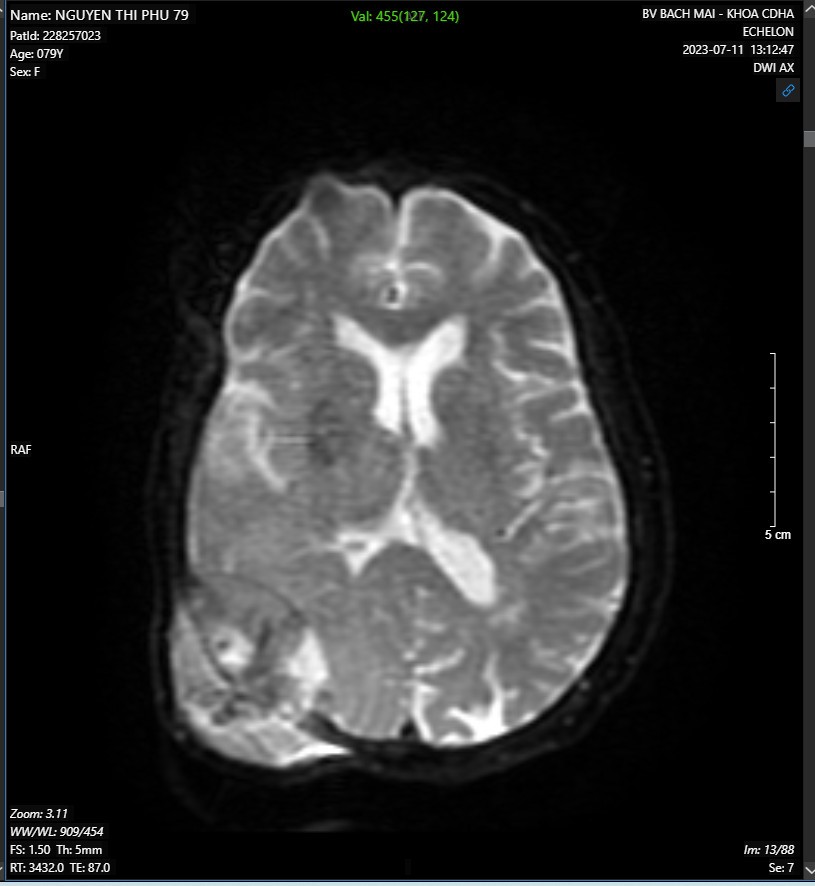

- MRI não-mạch não có tiêm thuốc đối quang từ:

Hình ảnh khối ngoài trục vùng thái dương-chẩm phải kích thước 48x50x60mm nghĩ nhiều đến khối u xương, có chảy máu trong u, gây tiêu xương sọ và xâm lấn phần mềm

Hình 2. Hình ảnh MRI não-mạch não có tiêm thuốc đối quang từ.